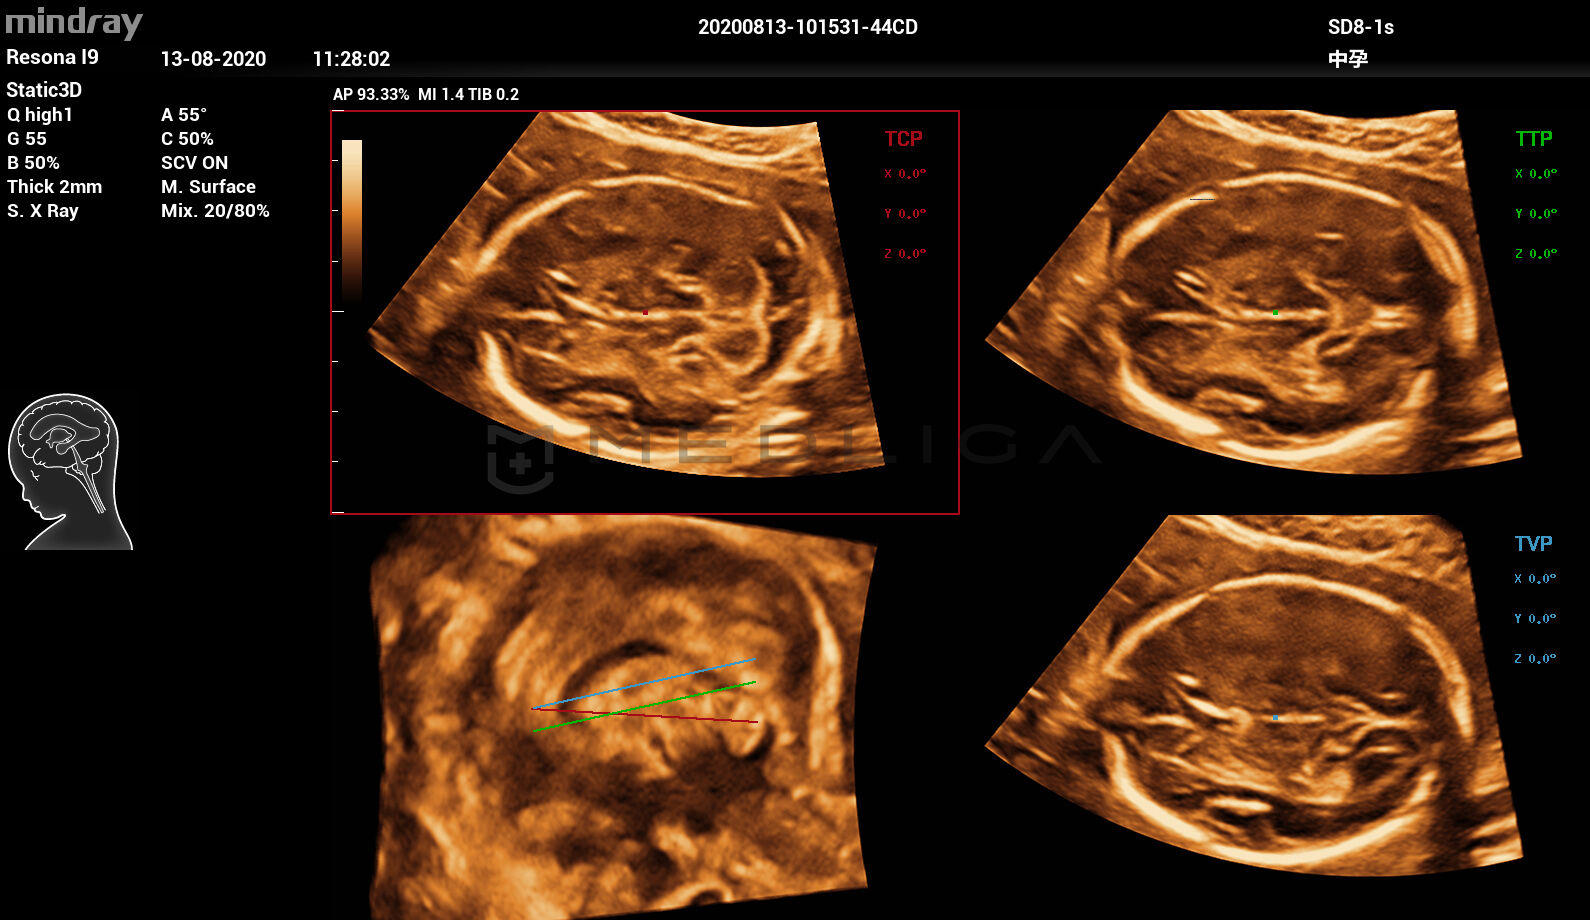

Smart Planes CNS – это удобный инструмент, который значительно повышает точность сканирования в сочетании с полностью автоматизированной работой, что обеспечивает точную диагностику, улучшенную пропускную способность и уменьшенную зависимость от пользователя.

• Полностью автоматическое распознавание срезов, 4 стандартных среза ЦНС

• TCP — трансцеребральная плоскость

• TTP — трансталамическая плоскость

• TVP — трансвентрикулярная плоскость